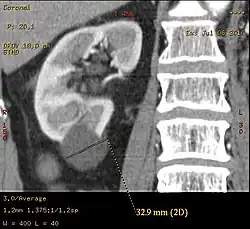

Non-contrast CT (at left) showing peripelvic fluid accumulations, which may be hydronephrosis. CT urography (at right) reveals non-dilated calyces and pelvises. The fluid accumulations are thus peripelvic cysts.

Parapelvic cysts originate from around the kidney at the adjacent renal parenchyma, and plunge into the renal sinus. Peripelvic cysts are contained entirely within the renal sinus, possibly related to dilated lymphatic channels. When viewed on CT in absence of contrast, they can mimic hydronephrosis.[15] If symptomatic, they can be laparoscopically decorticated - removal of the outer layer or cortex.[16]